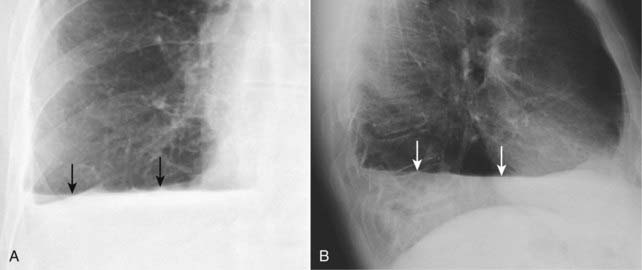

Figure 6-2 Right-sided subpulmonic effusion.

In the frontal projection (A), the apparent right hemidiaphragm appears to be elevated (solid black arrow). This edge does not represent the actual right hemidiaphragm, which has been rendered invisible by the pleural fluid that has accumulated above it, but the interface between the effusion and the base of the lung (thus the term “apparent hemidiaphragm”). There is blunting of the right costophrenic sulcus (solid white arrow). On the lateral projection (B), there is blunting of the posterior costophrenic sulcus (solid white arrow). The apparent hemidiaphragm is rounded posteriorly but then changes its contour as the effusion interfaces with the major fissure on the left side (solid black arrow).

Figure 6-3 Left-sided subpulmonic effusion.

In the frontal projection (A), more than 1 cm distance is seen between the air in the stomach and the apparent left hemidiaphragm (double black arrow). The edge between the aerated lung and the dotted white arrow does not represent the actual left hemidiaphragm, which has been rendered invisible by the pleural fluid that has accumulated above it, but the interface between the effusion and the base of the lung. There is blunting of the left costophrenic sulcus (solid white arrow) on both projections. On the lateral projection (B), the apparent hemidiaphragm is rounded posteriorly but then changes its contour as the effusion interfaces with the major fissure (solid black arrow).